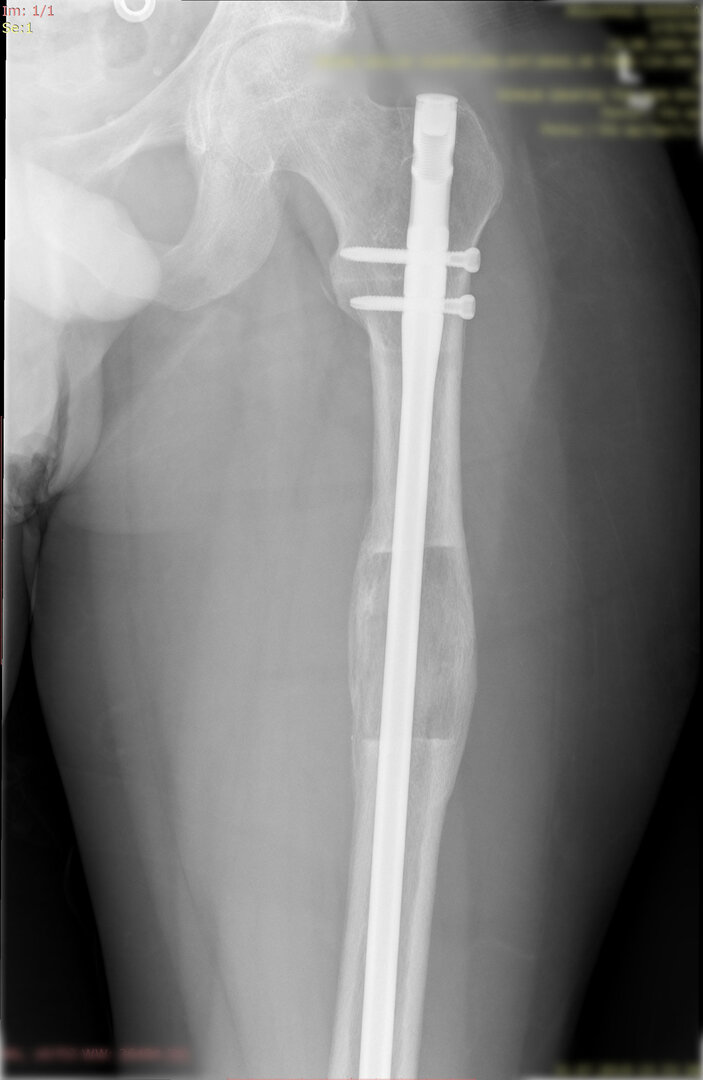

1. Kombine yöntem ile uzatma (LON-lengthening over nail- Çivi üzerinden uzatma):

Bu yöntemde uzatılacak kemiğin içerisine osteotomi sonrası bir intramedülller çivi yerleştirilir ve dışarıdan tek yönlü bir eksternal fiksatör kemiğe adapte edilir. Dışarıdan yine günde 4 defa çeyrek tur açarak 1 mm uzatma sağlanır. Uzatma miktarına ulaşılınca çivi kilitlenir ve uzayan bölümün sertleşmesi beklenir.

Görüntüleri büyütmek için üzerine tıklayınız.

Görseli büyütmek için üzerine tıklayınız. Görseli büyütmek için üzerine tıklayınız. Radyografi görseli büyütmek için üzerine tıklayınız. Radyografi görseli büyütmek için üzerine tıklayınız. Radyografi görseli büyütmek için üzerine tıklayınız.